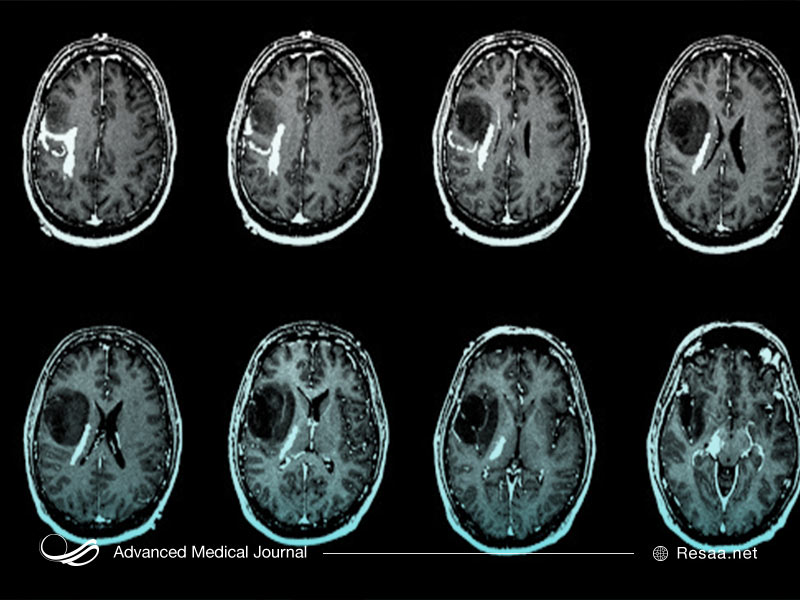

شایعترین انواع تومورهای اولیه مغز

بیش از 40 نوع تومور اولیه مغز و نخاع وجود دارد (که به آن سیستم عصبی مرکزی یا تومورهای CNS نیز گفته میشود). آنها براساس نوع سلول و نحوه رفتار سلولها (بر اساس ترکیب ژنتیکی آنها) طبقهبندی میشوند (همانطور که در زیر میکروسکوپ مشاهده میشوند). پزشکان از این طبقهبندی برای تشخیص بهترین درمان استفاده میکنند.